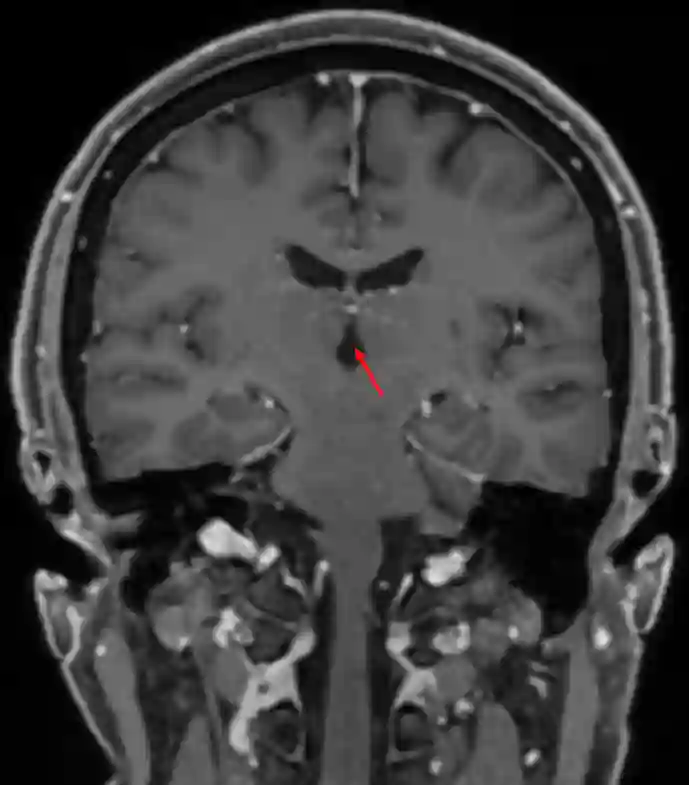

Dritter Ventrikel im MRI

Coronale T1 MRI Sequenz mit Kontrastmittel mit Darstellung des dritten Ventrikels.